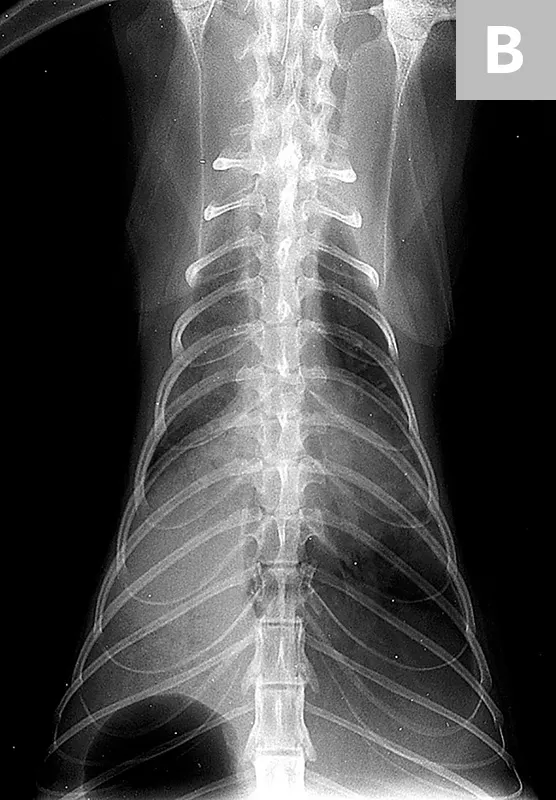

Hyperkeratotic hyperpigmented plaque on the nose, muzzle, and chin of a cat infected with papillomavirus

• Viral plaques are uncommon and are seen as single or grouped round-to-oval scaly, gray, tan, or black papules or plaques with hyperkeratosis (Figure 1).6 They are neither pruritic nor painful and may be present anywhere on the body. In healthy cats, they may resolve spontaneously.2 In immunosuppressed cats (eg, those with FIV, FIP, FeLV, or neoplasia; those receiving glucocorticoid treatment), resolution occurs after treating the primary cause. Demodex cati mites might be found in the lesions.1,6-9

FIGURE 1